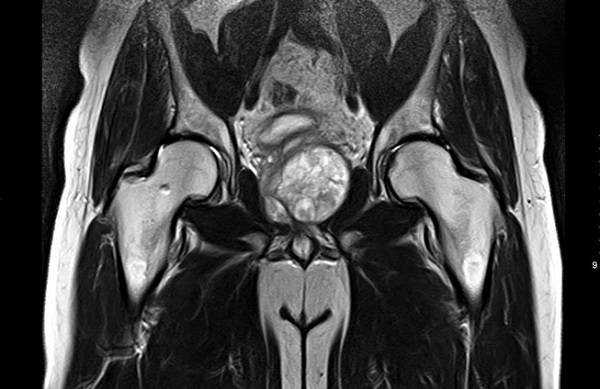

Артрит правого тазобедренного сустава на снимке МРТ

Магнитно-резонансное сканирование тазобедренных суставов